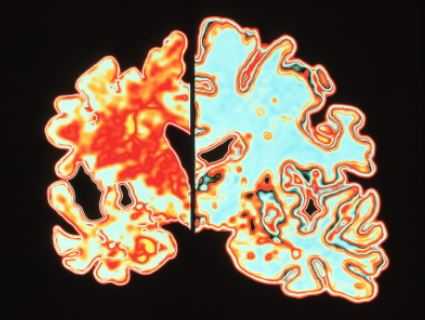

МРТ головного мозга. Демонстрация атрофии и нормы при цветовой обработке.

Под термином “нейродегенеративные заболевания” (НДЗ) определяется большая группа заболеваний преимущественно позднего возраста, для которых характерна медленно прогрессирующая гибель определенных групп нервных клеток и одновременно - постепенно нарастающая атрофия соответствующих отделов головного и/или спинного мозга. В основе развития этих заболеваний лежит нарушение метаболизма и изменение конформации клеточных белков с их последующим накоплением и агрегацией в определенных группах нейронов. При НДЗ страдают преимущественно нейроны и глиальные клетки базальных ганглиев и стволовых структур, вырабатывающие ацетилхолин, дофамин, серотонин.